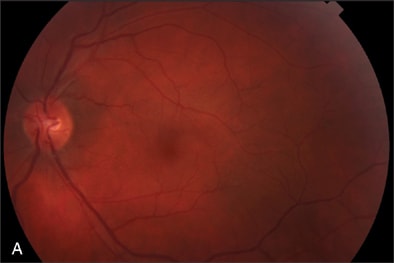

At our initial examination in August 2008, corrected visual acuity was 20/30 in the right eye and 20/50 in the left, with normal ocular pressure in both eyes. There were no rubeosis irides in either eye. Fundus examination appeared normal in the right eye while the left eye revealed a typical nonischemic CRVO (Figure 1A). Fluorescein angiography of the left eye (Figure 1B to 1E) showed generalized dilated, tortuous retinal veins, intraretinal hemorrhages, peripheral retinal non-perfusion areas, and microvascular leakage at the macula (Figure 1E, arrow). Despite the peripheral retinal ischemia, the macula itself was not ischemic at the first visit, as evidenced by the early phase FA showing 2 cilioretinal arteries supplying the fovea (Figure 1C, arrow). Spectral domain OCT (OPKO-OTI, Miami, FL.) confirmed the diagnosis of cystoid macular edema (CME). The patient got intravitreal bevacizumab (Avastin) injection (1.25 mg/0.05 mL) at the first visit.

At the 5-month follow-up visit in February 2009, corrected visual acuity remained 20/20 in the left eye, with normal ocular pressure in both eyes. There were no rubeosis irides in either eye. Fundus examination appeared normal in the right eye with improvement in the appearance of the retinal vasculature in the left (Figure 2A). Fluorescein angiography of the left eye (Figure 2B to 2E) showed resolution of the CRVO characteristics (dilated, tortuous retinal veins, intraretinal hemorrhages, peripheral retinal non-perfusion areas) with no microvascular leakage at the macula. Spectral OCT confirmed no cystoid macular edema (Figure 2E).